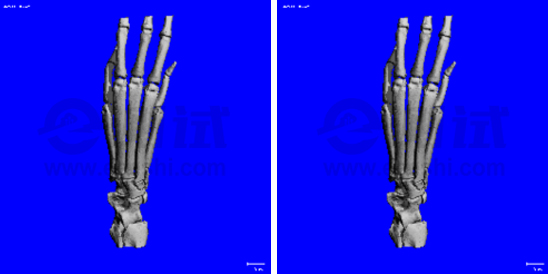

3. 骨質(zhì)疏松模型小鼠三維重建

a3370ee4dda9417dc558b2d3003e9cb4